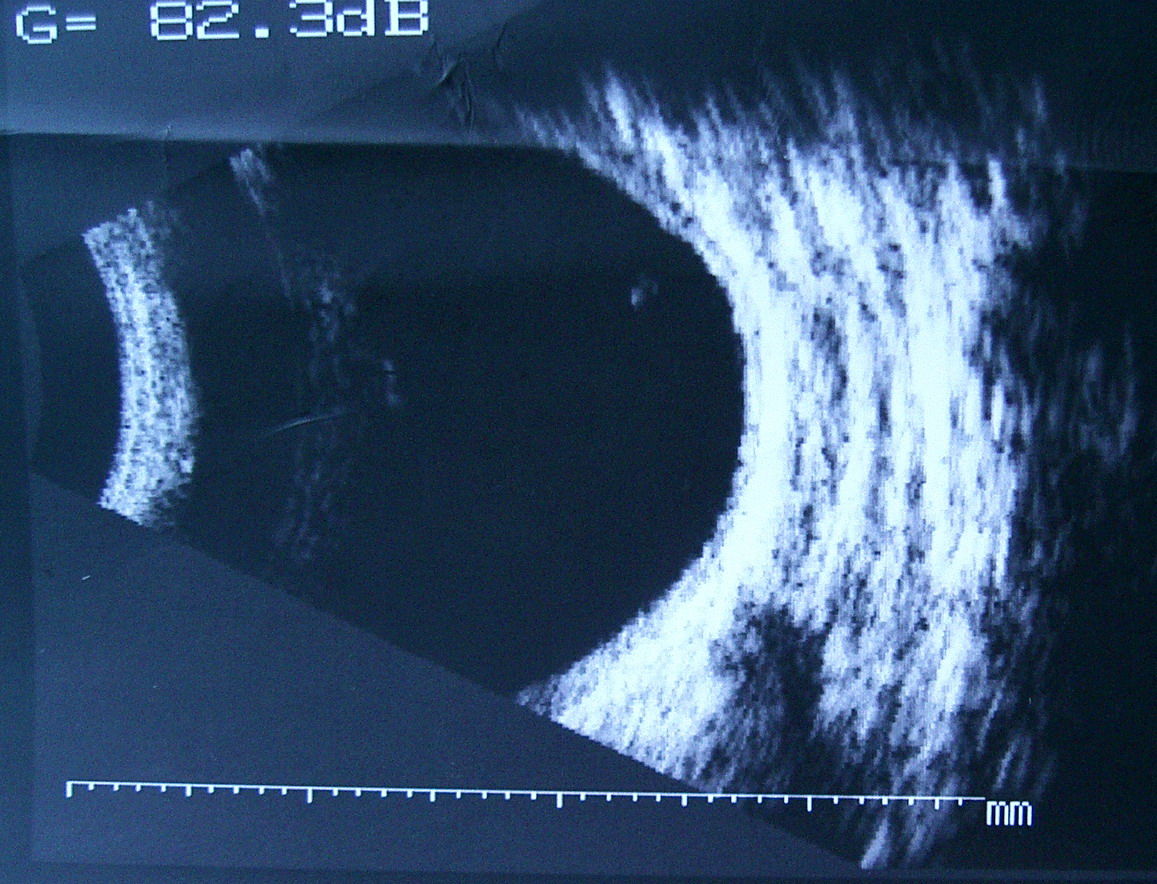

[B超]

此主题相关图片如下:

B超: OD:眶未见明显异常回声区。 OS:眶鼻侧见边界不清,回声强弱不均之异常回声区。 意见: 右眼眶未见占位性病变声像。 左眼眶可疑占位性病变声像。建议CT进一步检查。